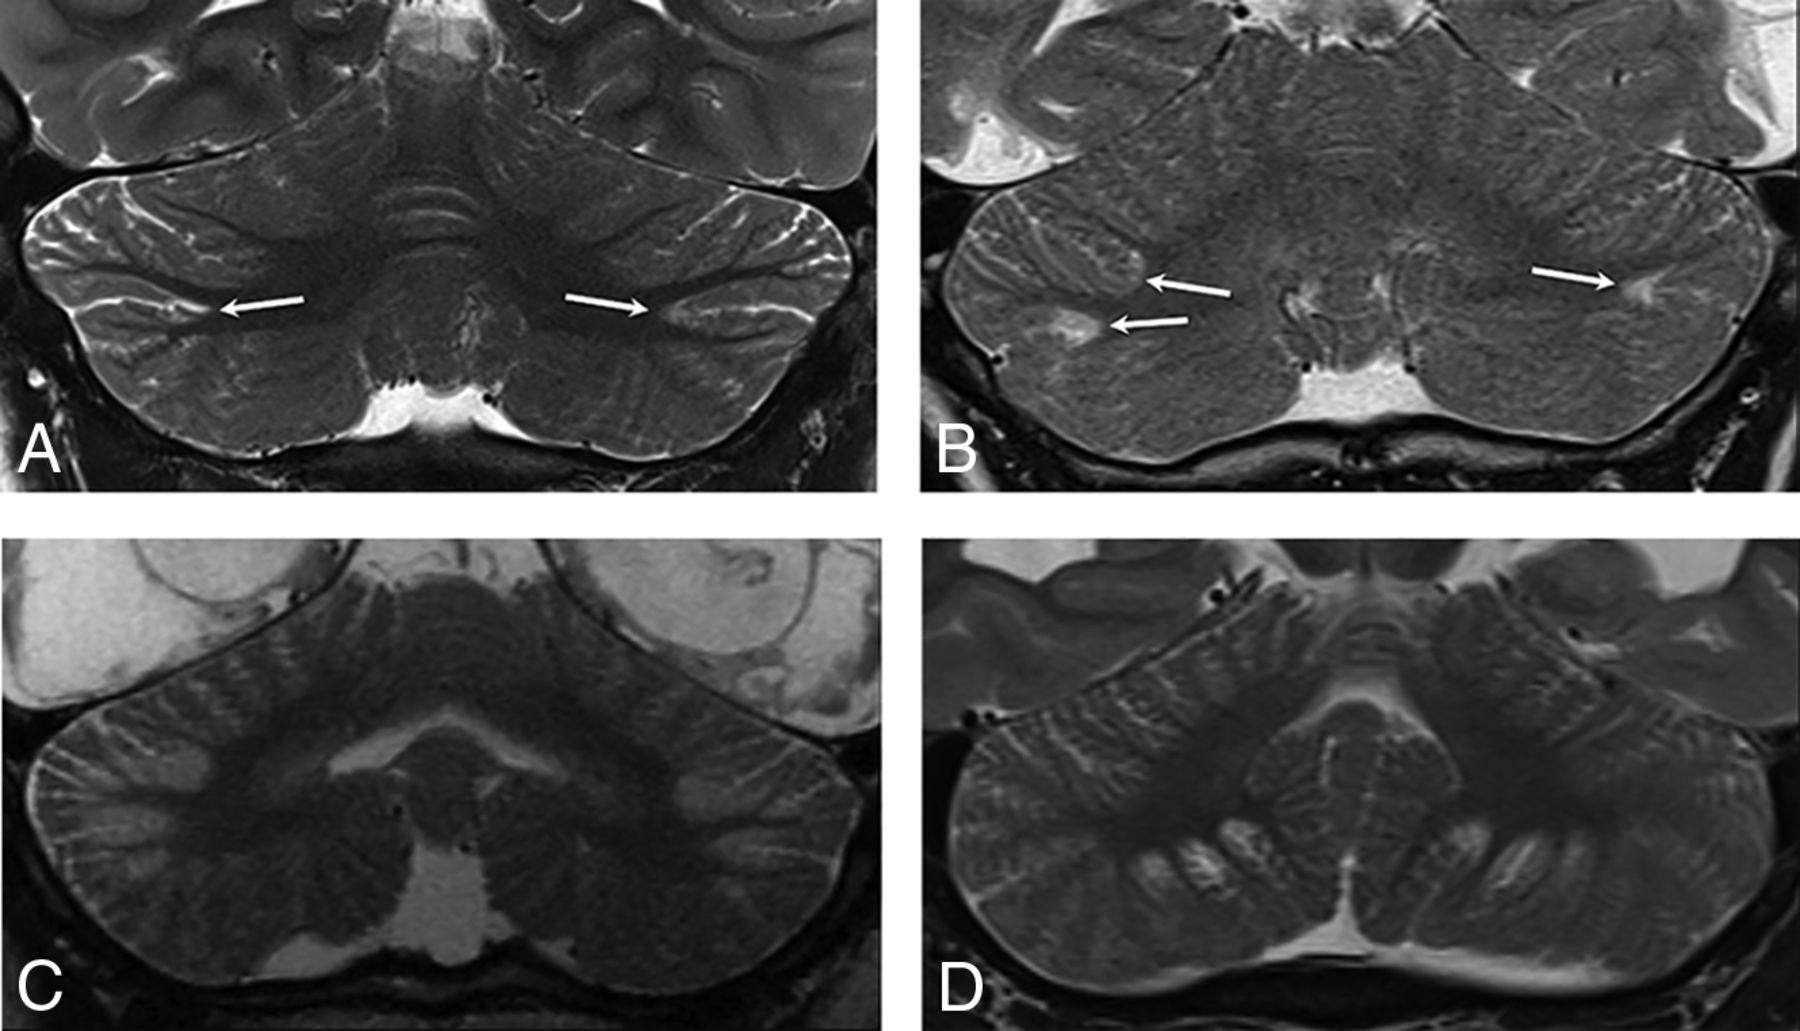

The key imaging feature was T2 and FLAIR hyperintensity and T1 hypointensity confined to the gray matter and immediate subjacent white matter at the depths of the cerebellar fissures (Fig 1). The findings were best seen on coronal and parasagittal fluid-sensitive sequences. In all patients, bilateral hemispheric involvement was present, with injury typically involving multiple fissures centered at the expected location of the borderzone between the superior cerebellar artery (SCA), AICA, and PICA (Fig 2). The cerebellar tonsils were injured in 39% (9/23) of cases. The cerebellar vermis was spared in 91% (21/23) of patients. Five of the 23 patients had prior imaging studies, all of which demonstrated a normal cerebellar cortex (Fig 3).

Axial T2WI from patient 2 (A), parasagittal T2WI from patient 8 (B), and a coronal T2WI from patient 6 (C) demonstrate the characteristic appearance and location of cerebellar watershed injury. There is T2 prolongation greatest in the gray matter at the depths of the cerebellar fissures (white arrows) within the deep cerebellar watershed territory.

Coronal T2WI from patient 4 (A, C, and E) and patient 11 (B, D, and F) demonstrates the appearance of newly developed acute (C and D) and subsequent chronic (E and F) phase injury in previously normal cerebella (A and B). White arrows highlight multipe sites demonstrating progressive development of typical watershed injury in previously normal gray matter.

Imaging was available for 16/23 patients during the acute phase of injury, defined as <7 days from the suspected clinical event. All patients demonstrated normal thickness or a mildly thickened cerebellar cortex (Figs 3 and 4). Eighty-one percent (13/16) of patients demonstrated acute diffusion restriction (12 with an eventual clinical diagnosis of HII, 1 of unknown etiology) (Fig 4A–C), while 19% (3/16) of patients demonstrated no diffusion abnormality (all with an eventual clinical diagnosis of PRES) (Fig 4D–F). The 3 patients with PRES were imaged in the acute phase only, with no imaging follow-up available.